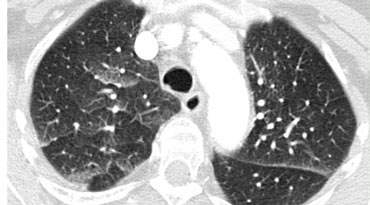

The CT chest image shows a hazy increased attenuation with preserved bronchial and vascular markings. What pattern is demonstrated?

Explanation: ***Ground glass pattern*** - The image shows **hazy increase in lung attenuation** that does not obscure underlying bronchial and vascular margins - This is the defining feature of **ground glass opacity (GGO)** - Suggests partial filling of airspaces, interstitial thickening, partial alveolar collapse, or increased capillary blood volume - Commonly seen in **interstitial lung diseases**, atypical pneumonias, pulmonary edema, and diffuse alveolar hemorrhage *Honeycomb pattern* - Characterized by **clustered cystic airspaces** with thick walls (3-10mm) - Represents **end-stage pulmonary fibrosis** with irreversible architectural distortion - Typically seen in **peripheral and subpleural distribution** in usual interstitial pneumonia (UIP) - NOT present in this image, which shows preserved architecture *Crazy paving pattern* - Combination of **ground glass opacity with superimposed interlobular septal thickening** and intralobular lines - Creates a pattern resembling **irregular paving stones** - Classically associated with **pulmonary alveolar proteinosis** but also seen in Pneumocystis pneumonia, ARDS, and organizing pneumonia - NOT present in this image, which lacks the prominent septal thickening *Tree-in-bud pattern* - Represents **centrilobular nodules** with connecting branching linear structures - Indicates **bronchiolar impaction** with mucus, pus, or fluid - Commonly seen in **endobronchial spread of tuberculosis**, bacterial bronchopneumonia, and bronchiolitis - NOT present in this image, which shows diffuse hazy attenuation rather than nodular opacities